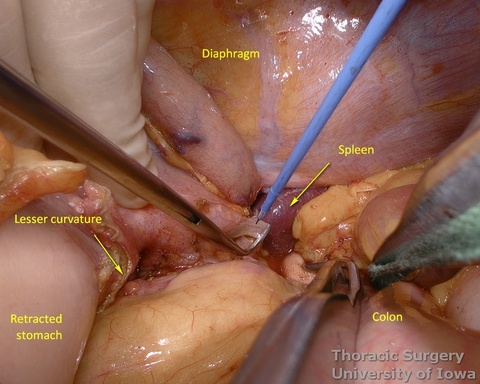

- Fundus of the stomach is dissected free all the way to the esophageal hiatus dividing gastro-phenic ligament and remaining adhesions.

- Once the stomach is mobilized and reflected anteriorly, the left gastric vascular pedicle is identified and dissected close to the origin for adequate lymphadenectomy. Care is taken to not injure splenic artery and pancreas.

- Left gastric vessels are divided with an endoscopic linear cutting stapler proximally, including all adjacent lymph nodes in the specimen.